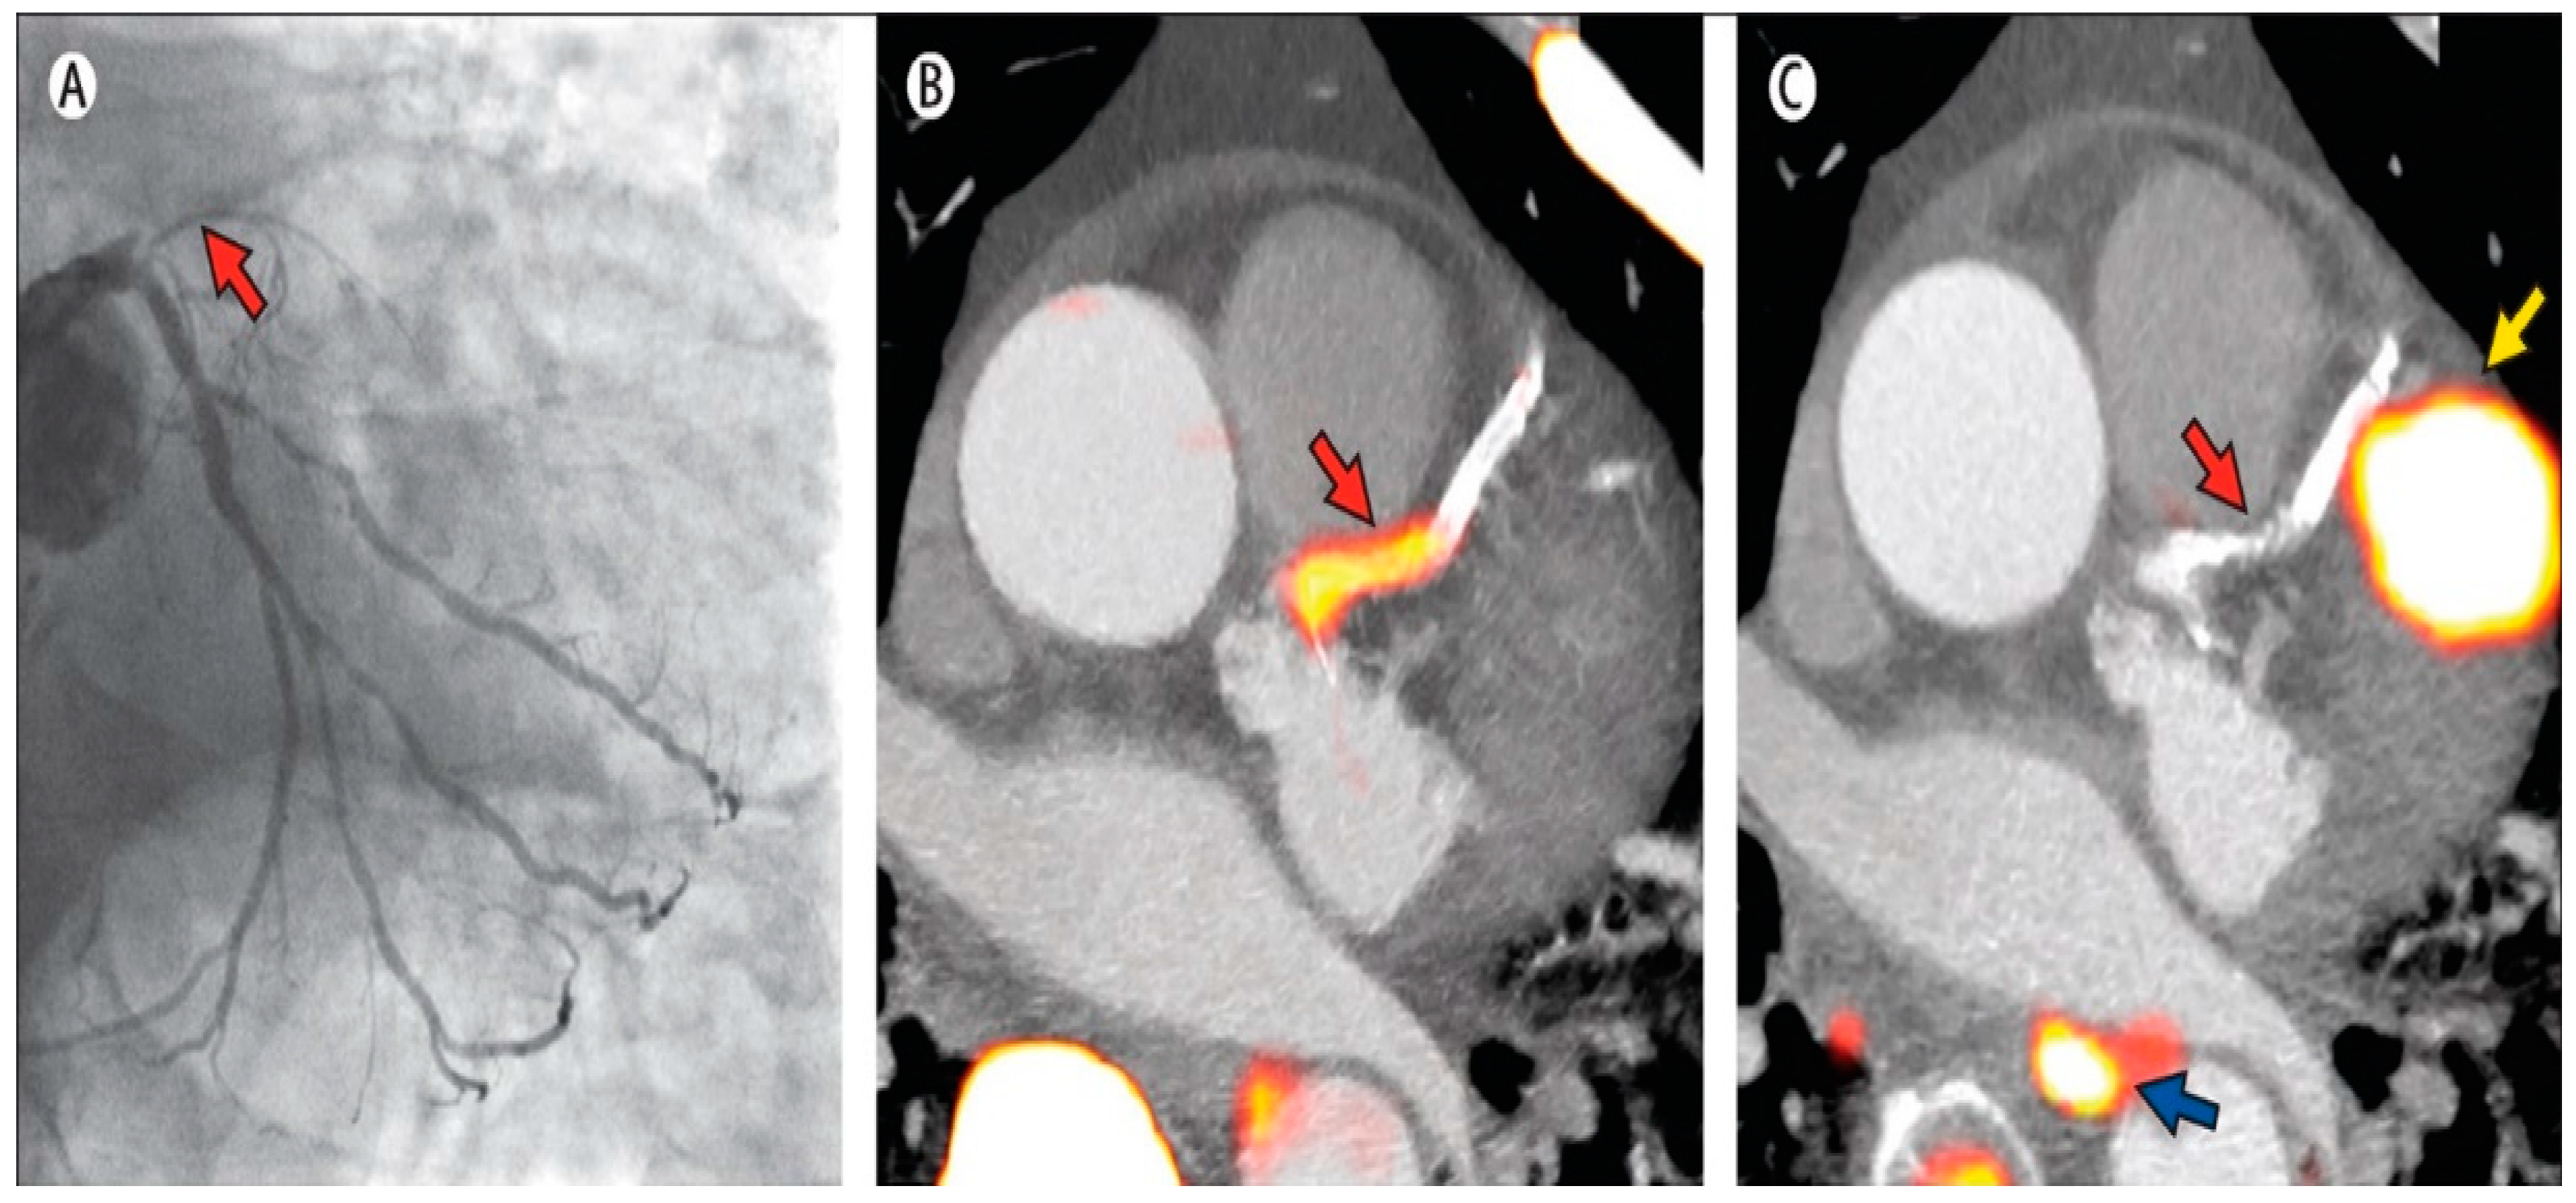

4. PET-CT Studies

4.1. MPI and Diagnostic Accuracy of CAD

4.2. Risk Stratification and Management